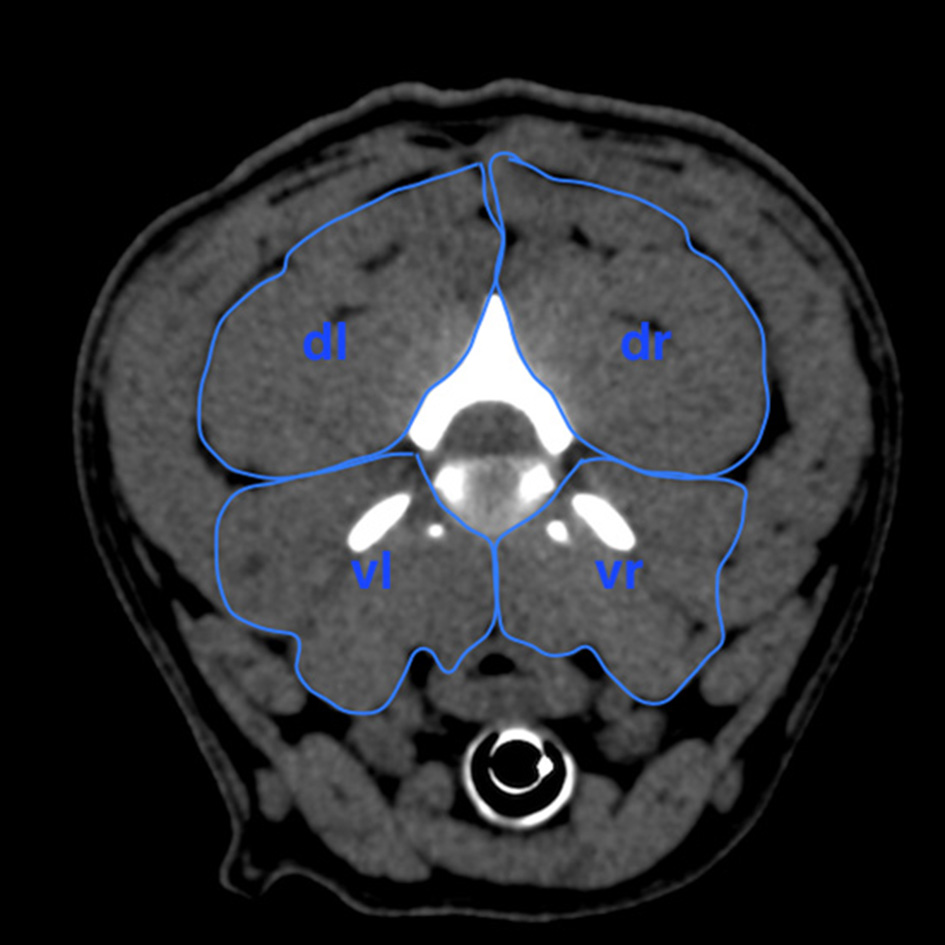

The areas of the cervical paraspinal muscle groups were outlined on the CT image at each IVD space of the cervical spine (Figure 4) to show the muscle mass of the dorsal and ventral parts of the transverse plane. The computer program was used to calculate the values of these areas. Muscle groups of the paraspinal musculature were divided into dorsal and ventral, left and right areas leading to a ventral right (vr) and a ventral left (vl) muscle area, which were added up to the ventral paraspinal musculature (vrl). Dorsal right (dr) and dorsal left (dl) muscle areas were added up to the dorsal paraspinal musculature (drl). Finally, the area ratio for each cervical segment was calculated by dividing drl by vrl (1). Mean area ratios of both the IVDH and BOAS groups were determined to evaluate statistically significant differences.

Figure 4

Scheme of measurement of the areas in the four quadrants of the cervical paraspinal musculature at the intervertebral disk level of C2/C3 in transversal plane to calculate area ratio. dr, dorsal right area; dl, dorsal left area; vr, ventral right area; vl, ventral left area.